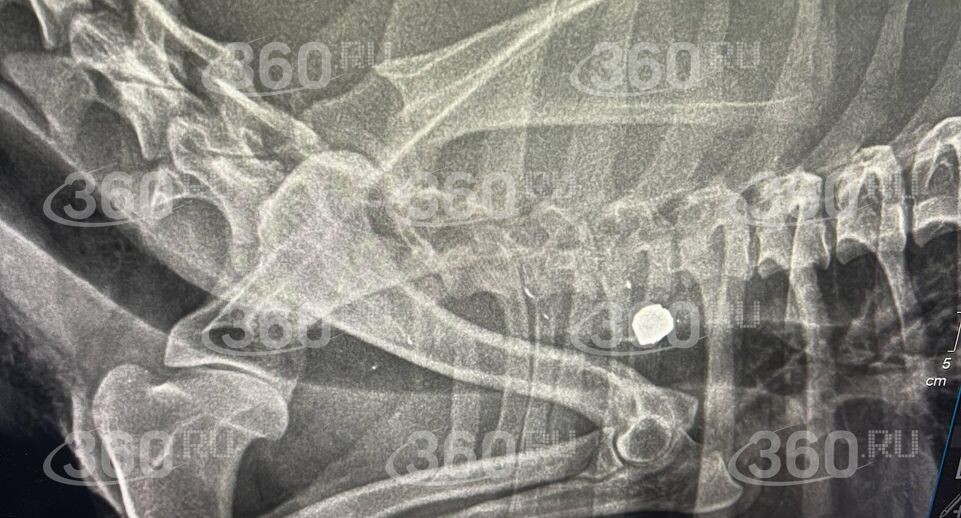

Она отвезла пса в ветеринарную клинику, при обследовании специалисты нашли пулю.

«Сделали рентген. Пуля в труднодоступном месте, оперировать не стали», — добавила собеседница 360.ru.